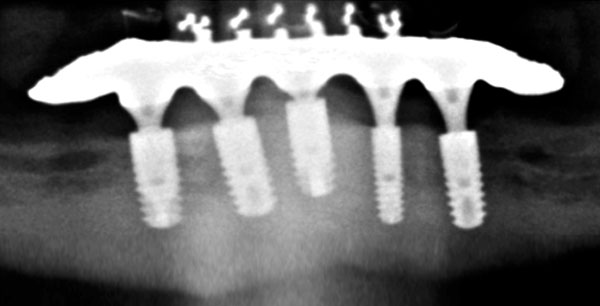

FOTO Abschlußröntgenbild der Versorgung |

OPG Steganprobe